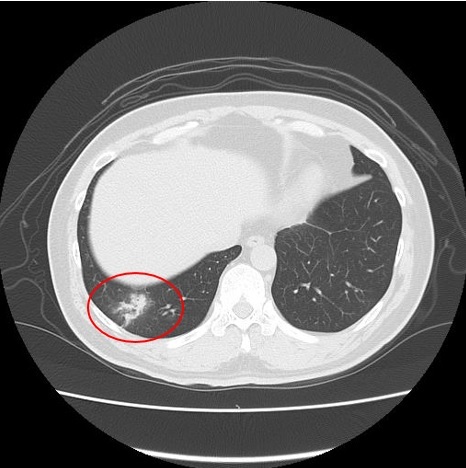

▼CT検査で得られる画像

例1 肺炎